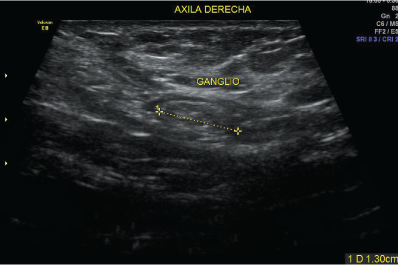

La ecografía mamario utiliza ondas sonoras para producir fotografías de las estructuras internas del seno.

Se utiliza primariamente para ayudar a diagnosticar bultos en el seno u otras anormalidades que su médico podría encontrar durante un examen físico, una mamografía o una RMN del seno.